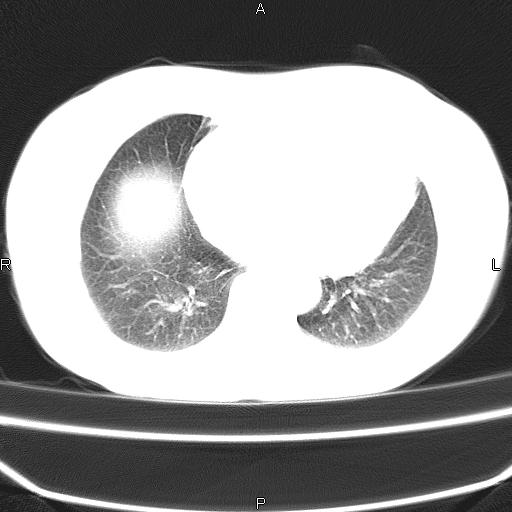

患者,女,66岁。健康体检胸部透视发现右上肺片状阴影。既往无不适,患者自诉三个月前曾有低热病史体温37.5左右一周。用药后缓解。至今无其它不适。请老师们指导指导。

考虑:右肺上叶周围型肺癌(分叶状肿块+砂粒状钙化+胸膜尾征)。

病灶见明显分叶、大小较大(大于3cm?),老年人,多考虑:肺癌,建议穿刺活检。

典型的中心型肺癌,尖段支气管阻塞。

以下是引用dyqct在2010-6-3 9:32:00的发言:[br]考虑:右肺上叶周围型肺癌(分叶状肿块+砂粒状钙化+胸膜尾征)。

右肺上叶周围型肺癌可能性大。

考虑:右肺上叶周围型肺癌